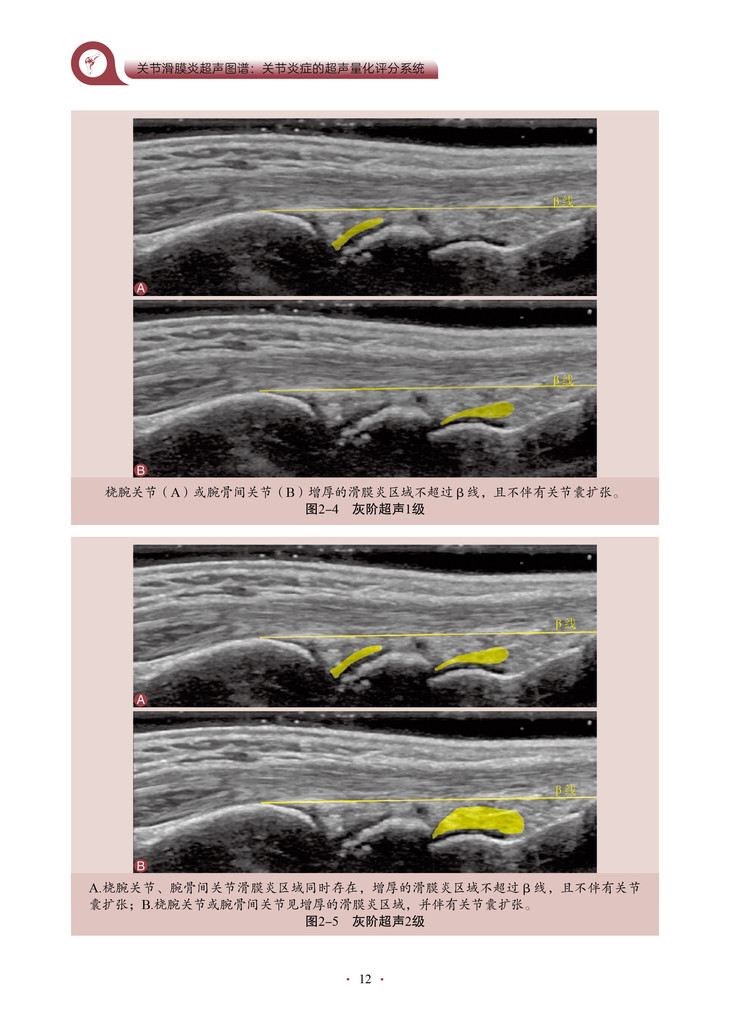

本书的核心内容是将超声技术应用于关节炎程度的评估,特别是对关节滑膜炎症的评分和客观量化。通过详细地介绍超声评分系统的构建和应用,作者为我们展示了一种全新的、基于客观指标的关节炎评估方法。该书深入探讨了关节滑膜超声图像的解读和分析,教导读者如何识别和评估关节炎引起的滑膜病变。通过使用可靠的超声评分系统,医师和研究人员能够更准确地量化关节炎患者的炎症程度和疾病进展,从而更好地指导治疗和监测疗效。